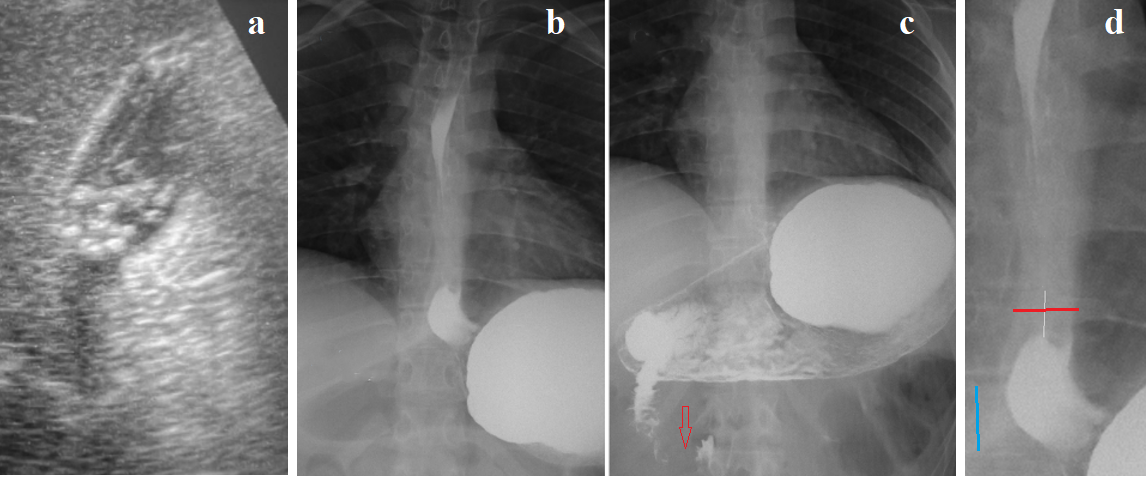

For example, the isolation of EoE as an independent disease contradicts studies showing that EoE is part of a group of eosinophilic gastrointestinal diseases (EGIDs) with chronic inflammation of the gastrointestinal tract, which are characterized clinically by symptoms related to the dysfunction of the involved segment(s) of the GI tract and histologically by dense eosinophilic inflammation, in the absence of an identifiable secondary cause.The group of EGIDs comprises EoE, eosinophilic gastritis, eosinophilic gastroenteritis, and eosinophilic colitis. Eosinophilic infiltration can be found in several parts of the digestive tract in one patient [15]. Mahendra et al showed that duodenal eosinophilia was associated with symptomatic erosive GERD [16]. Eosinophilic infiltration of the antrum causes marked thickening of the gastric wall, which is not involved in peristalsis. This type of gastritis is called "rigid antral gastritis" (RAG) [17]. (Figure 2).

Figure 2. Radiographic appearance of rigid antral gastritis (RAG). (a) A 19-year-old overweight woman complained of abdominal pain. She began vomiting after eating six months ago. During this time, she lost 5 kg. A gastroscopy diagnosed GERD. No pathology was found in the stomach or duodenum. She is allergic to chicken feathers. X-ray examination during high pressure in the stomach revealed: 1. The gastric antrum is narrowed, straightened, with thickened walls and a narrow lumen, consistent with the appearance of rigid antral gastritis (RAG). 2. The duodenal bulb (d) is irregularly shaped. In the third part of the duodenum, contraction of the sphincter of Ochsner (red line) is visible, indicating hypersecretion of hydrochloric acid. (b) A normal gastroduodenal radiograph is shown as an example. Antral peristalsis begins with contraction of the antral sphincter (arrow). The antrum (a) has elastic walls and a wide lumen. The duodenal bulb has a typical arrowhead shape. (c-d) Examples of RAG.

The combination of GERD with impaired gastric emptying due to antral stenosis and thickened walls, along with dyskinesia of the duodenal bulb and Ochsner sphincter, coupled with allergies, allows for a diagnosis of hydrochloric acid hypersecretion with damage to the esophagus, stomach, and duodenum, with eosinophilic infiltration of the walls of the affected segments of the gastrointestinal tract. These data indicate that hydrochloric acid is the primary damaging factor causing the inflammatory process. The body's allergic reaction transforms the inflammation into eosinophilic infiltration.

Ultrasound of the abdomen. Multiple small stones in the gallbladder without signs of inflammation (Figure 3а). Figure 3 shows radiographs taken at maximum gastric pressure (Figure 3b) and after 5 minutes at rest (Figure 3c).

Figure 3. Examination of a 16-year-old girl. (a) Small stones in a contracted gallbladder. (b) Radiograph taken during straight legs raise at the end of a continuous barium drink. Contrast medium is absent between the 6th and 8th thoracic vertebrae above the phrenic ampulla. A significant amount of barium is in the stomach, indicating good fluid permeability through the esophagus. The diagram of this radiograph (Figure d) shows thickening of the walls in the lower part of the esophagus and shortening of the LES (the distance between the ampulla and the stomach). (c) After 5 minutes at rest, finely wavy contours of the second part of the duodenum and contraction of the sphincter of Ochsner (red arrow) are visible.

Based on medical history, clinical presentation (dysphagia, abdominal pain, GERD, allergy), and radiological findings (gallstones, lower esophageal wall thickening, shortening of the LES, and duodenal dyskinesia, including contraction of the Ochsner sphincter), a diagnosis of hydrochloric acid hypersecretion, GERD, and duodenal dyskinesia was made. Taken together, these findings suggested the possibility of EoE. Endoscopy with a lower esophageal biopsy was recommended. Endoscopy revealed no esophageal pathology, diagnosed nodular gastritis, and found some erosions in the duodenal bulb. Histological examination revealed no esophageal or gastric pathology. However, no specific eosinophil count was performed. I recommended continuing the PPI and antiallergic medication, lying down only on an empty stomach, and avoiding lactose-containing products. From then (2021) to today (2025), the patient has been feeling well. She is studying at university and has not seen any more doctors.